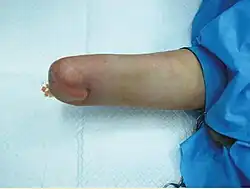

Im ersten Jahr nach der Transplantation machen ca. 85 % der Patienten eine Abstoßungsreaktion durch,[62] welche sich im Normalfall jedoch gut mit einer simplen Erhöhung der Dosis an Immunsuppressiva oder dem zusätzlichen Einsatz von Glucocorticoiden behandeln lässt. Der Vorteil gegenüber einer „normalen“ Organtransplantation liegt dabei darin, dass sich eine Abstoßung bei einer Handtransplantation leicht an einer Verfärbung der Haut, einem Anschwellen der Hand und an Hautbiopsien erkennen lässt.[54]